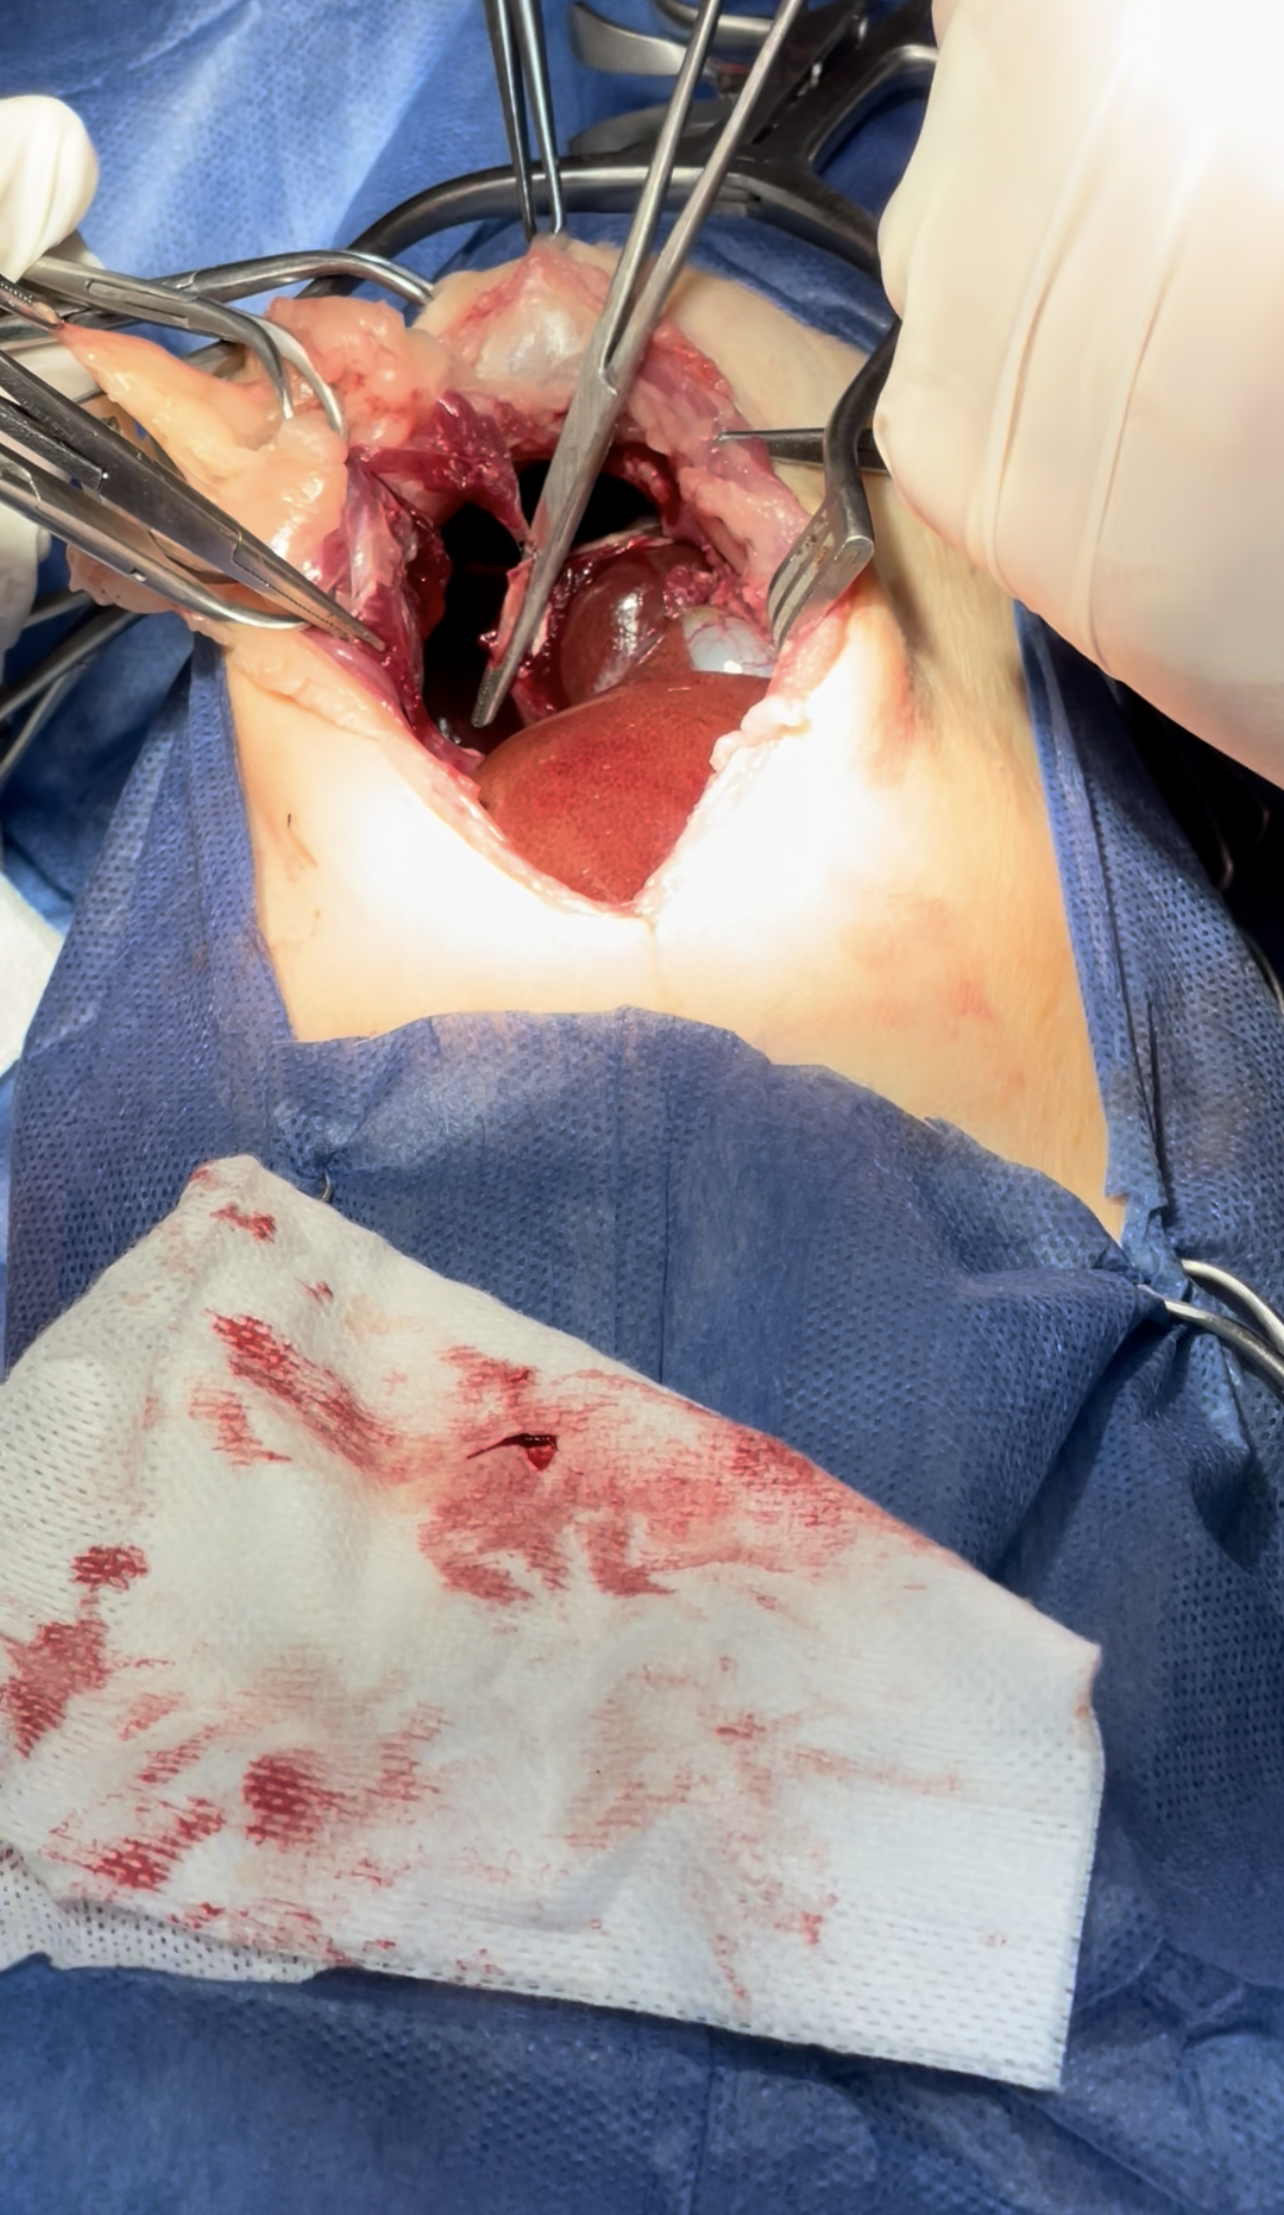

Widening the herniation to allow organ exteriorization

Lacerations while dissection compressed with Gelfoam to minimize the parenchymal injury